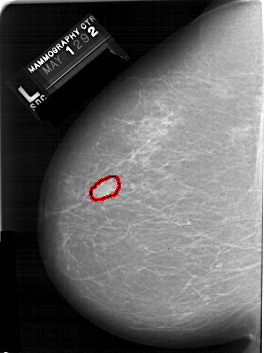

A_1128_1.LEFT_MLO

FILE: A_1128_1.LEFT_MLO.OVERLAY

TOTAL_ABNORMALITIES 1

ABNORMALITY 1

LESION_TYPE MASS SHAPE IRREGULAR MARGINS ILL_DEFINED

ASSESSMENT 4

SUBTLETY 5

PATHOLOGY MALIGNANT

TOTAL_OUTLINES 1

BOUNDARY